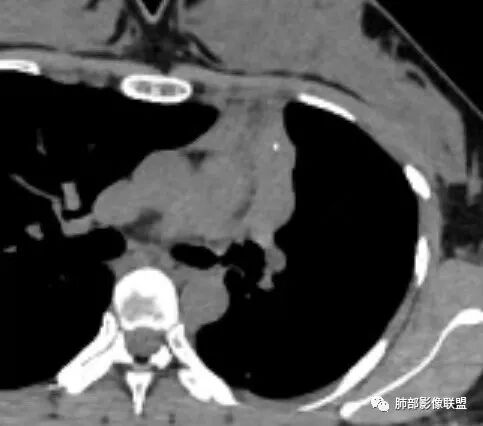

胸部CT:左肺体积缩小,左肺上叶前段纵隔旁胸膜下大片实变影,边缘清楚、匀齐、平直收缩,部分略膨隆,周围多发结节、树芽卫星灶,纵隔窗病灶与纵隔胸膜黏连,实变内多发点状钙化。平扫密度尚均匀,增强扫描不均匀明显强化,多个低密度区,呈仙人掌样,伴有条状血管影,考虑慢性炎症伴左上叶前段支气管闭塞,TB?鉴别黏表、腺癌等。

3.病灶内未强化液性低密度区,粘液可能性较大。

7.关于病灶的部分显著强化,及肺结核灶常有,也非粘液表皮样癌特点。但如强化部分为周围萎陷肺组织,则另当别论。